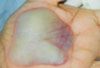

A 42-year-old homemaker noticed a discoloration on her palm. There were no symptoms, but she was greatly perturbed by her inability to wash this “dirt” off her skin . . .